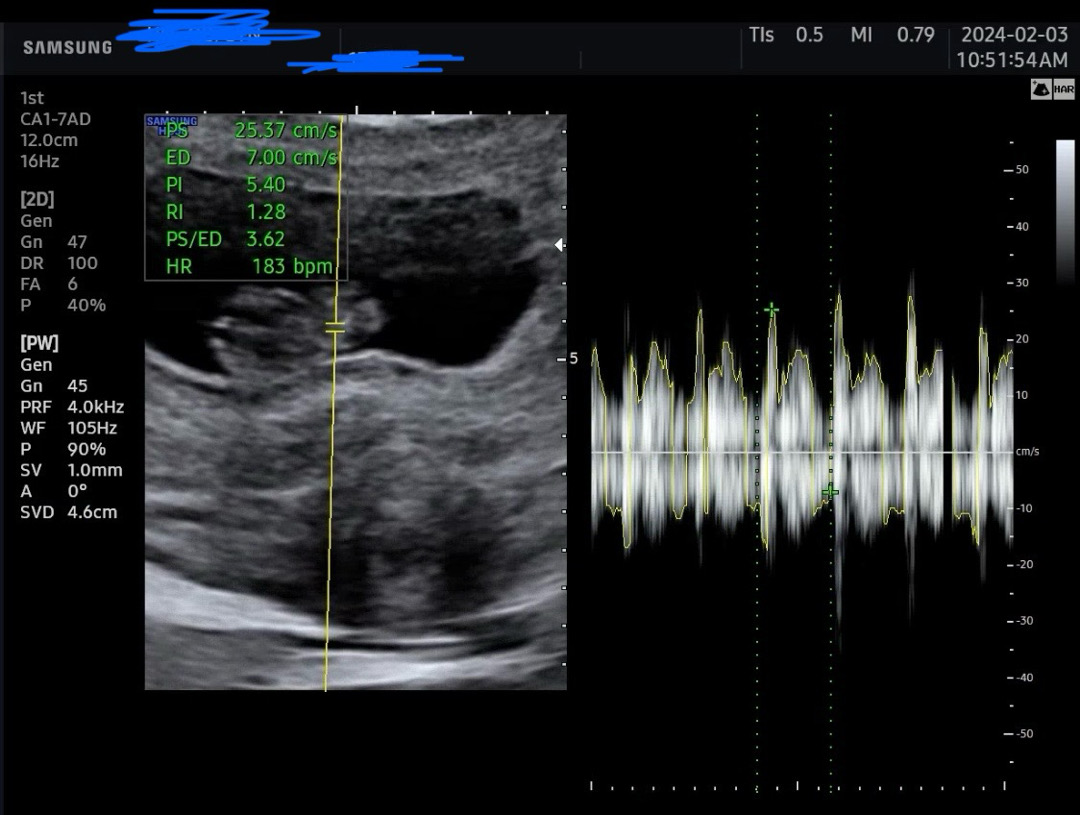

9주2일🩷 심장소리

오늘 심장소리 처음 듣고왔어요!!!! 우렁찬 심장소리 ㅎㅎㅎㅎ 가끔 갈색냉이나혈이나와서 걱정했는데 의사쌤이 건강하게 크고있다고 하시니까 기분 좋아요😊